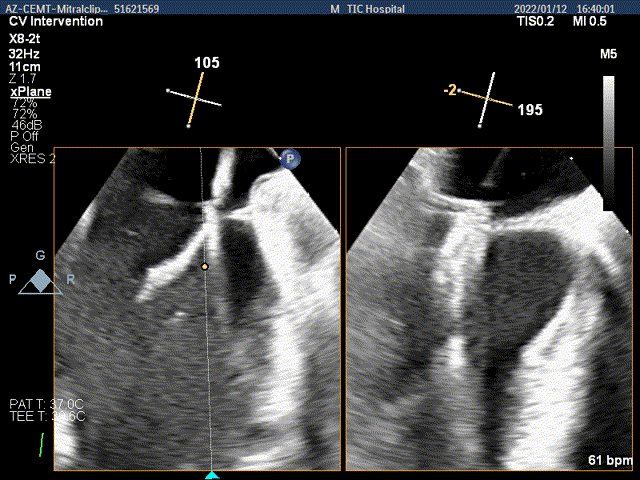

3Dview验证两个夹子的位置是否平行

抓捕内侧残余脱垂,color-view示残余返流逐渐减少,主要来源于两个夹子之间

第二个夹子放置侯二尖瓣口平均跨瓣压差:3mmHg

肺静脉血流频谱完全恢复正向

x-plane验证前后叶抓捕后跳跃征明显

3D-view验证两个夹子位置稳定,排列紧密

3D-Color-view验证微少量残余返流